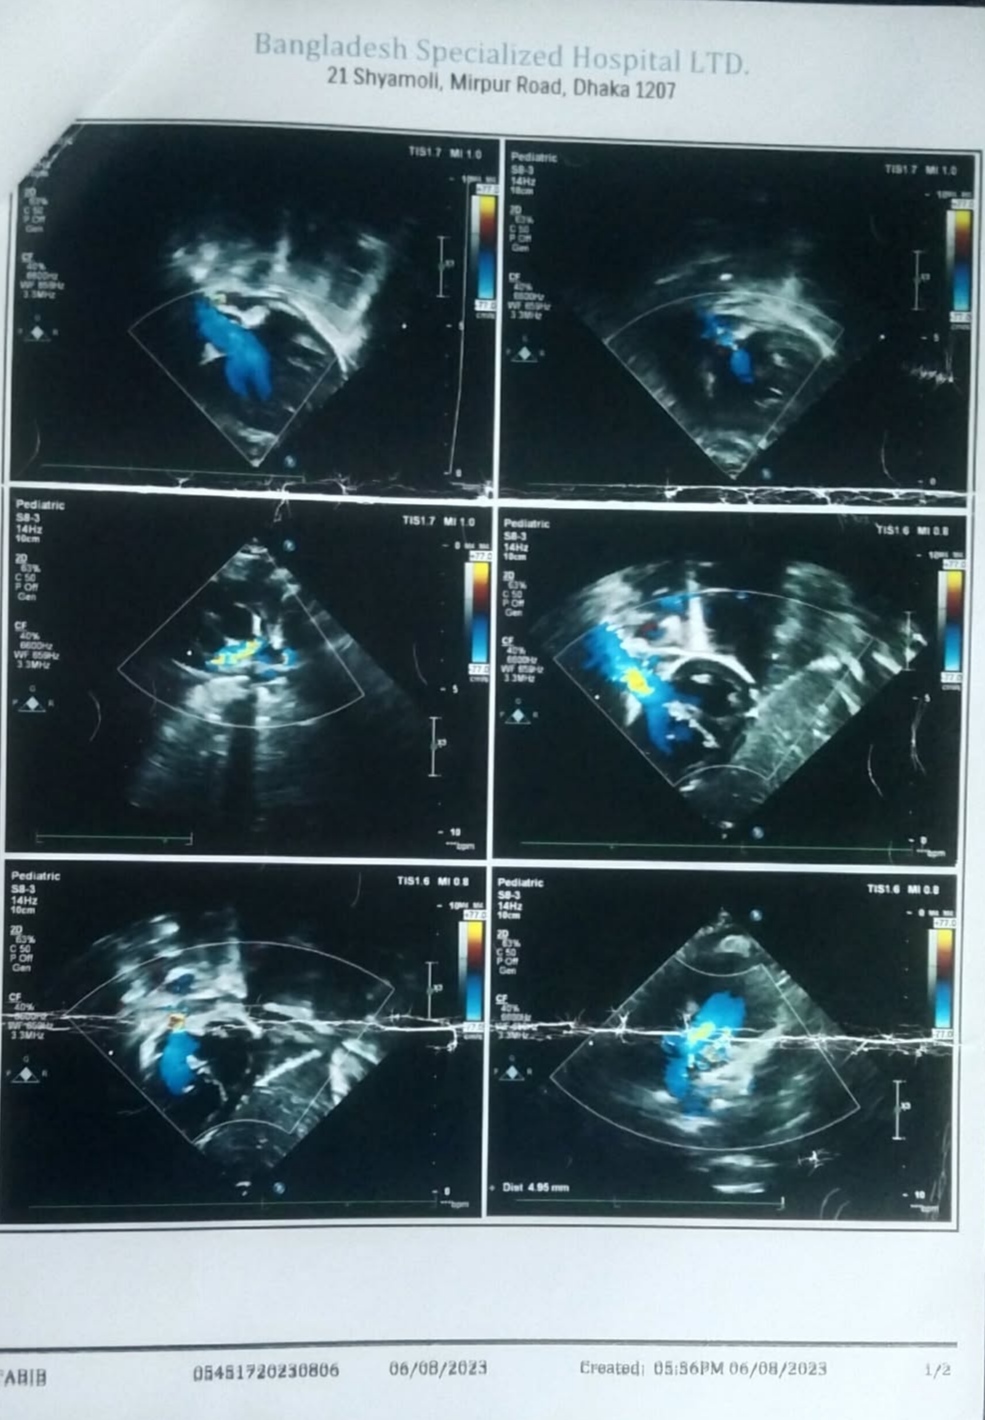

#250927A: হৃদরোগে আক্রান্ত আব্দুর রহমান তাবিদের ওপেন হার্ট সার্জারির জন্য সাহায্যের আবেদন, গ্রাম: বিন্নাটি, জেলা: কিশোরগঞ্জ।।